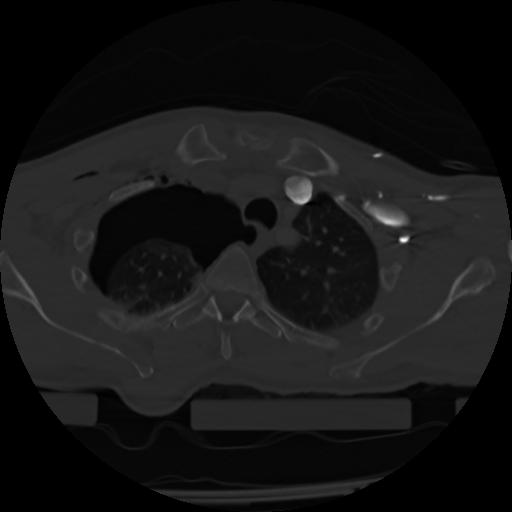

21 ANGIO,CE,Axial,3.0,ANGIO,,